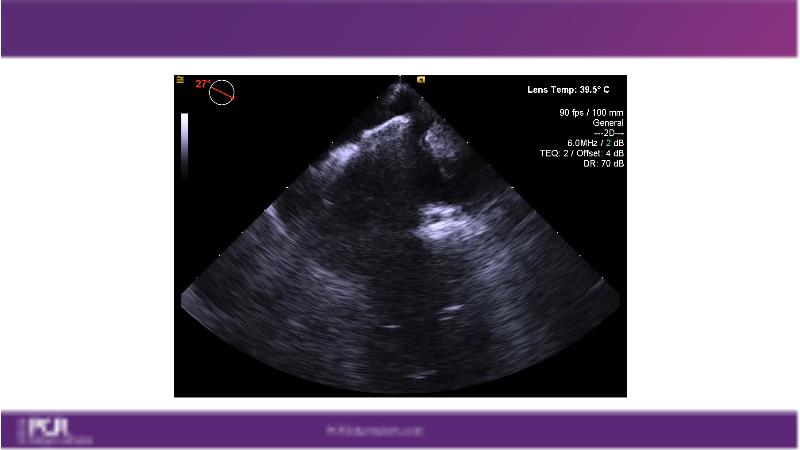

Watch this session to get an overview of a new TEER device, follow the step-by-step procedure related to initial experiences with this device for a Japanese patient with degenerative mitral regurgitation, learn about the latest data from RCT and registries, and follow discussions of challenging TEER cases!

- To learn procedural step-by-step of novel device